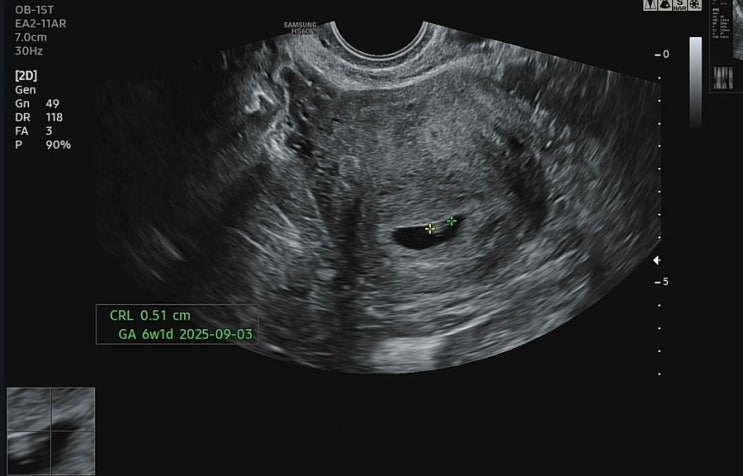

안녕하세요 별이맘스리입니다 기형아검사는 1, 2차 두 번 실시해서 최종 결과가 나오도록 진행이 됩니다 다...